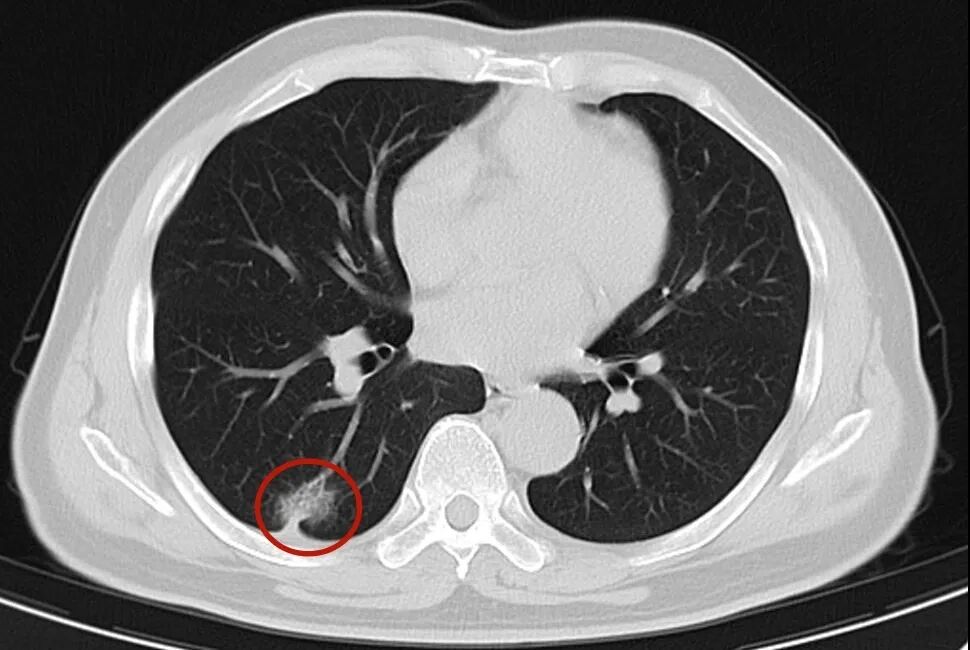

在我院心胸外科诊室,64岁的陈叔攥着CT报告,声音忍不住地颤抖。一次普通的社区体检,竟发现他右肺有一个“混杂磨玻璃结节”,报告上“Lung-RADS 4A类”的字眼,让他几天几夜没睡好。

(图为陈叔的CT报告,红圈处为结节)

陈叔身体一向硬朗,这次的体检结果却让他和家人心头一紧。我院心胸外科主任伊严仔细阅片后,结合结节长期存在的特点,判断:“这个‘磨玻璃结节’很可能就是早期肺癌的信号,必须尽快处理!”